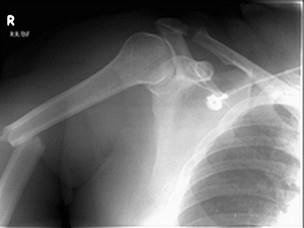

问题 30岁男性,外伤,查体:上臂较对侧短4cm,有轻度成角畸形,听诊骨传导音明显减弱,X线片见图,骨折的移位是 ( )

选项 A、混合移位 B、侧方移位 C、成角移位 D、分离移位 E、短缩移位

答案 A